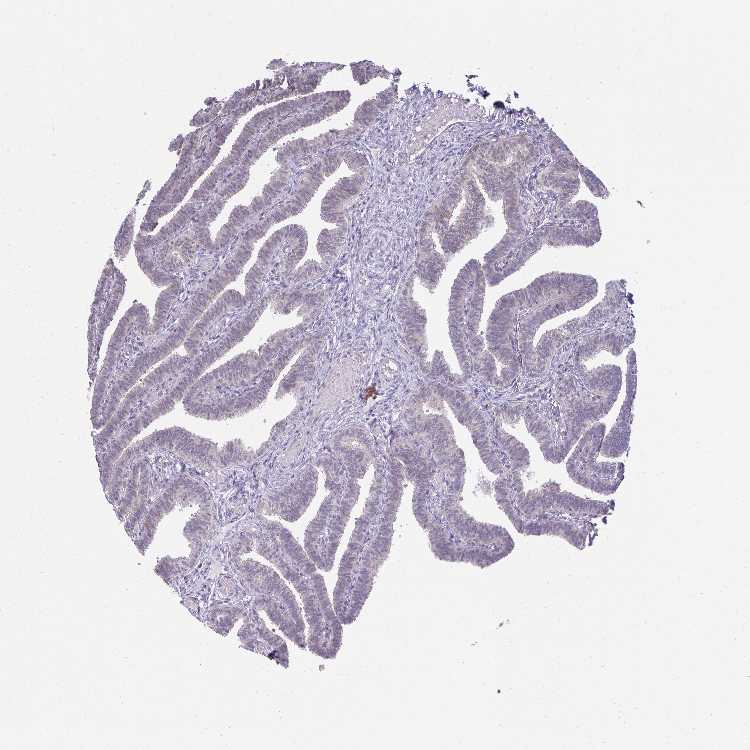

TISSUE PRIMARY DATA FALLOPIAN TUBE Show tissue menu

FALLOPIAN TUBE - Antibody stainingi

Antibody staining in the annotated cell types in the current human tissue is reported as not detected, low, medium, or high, based on conventional immunohistochemistry profiling in selected tissues. This score is based on the combination of the staining intensity and fraction of stained cells.

Each image is clickable and will lead to virtual microscopy that enables deeper exploration of all samples and also displays staining intensity scores, fraction scores and subcellular localization as well as patient and tissue information for each sample.

Antibody HPA058076

Ciliated cells (cell body) Medium

Ciliated cells (cilia axoneme) Not detected

Ciliated cells (ciliary rootlets) Medium

Ciliated cells (tip of cilia) Low

Non-ciliated cells Medium